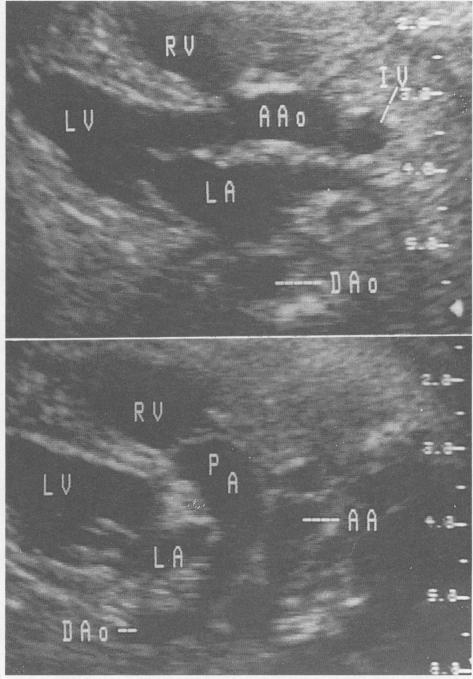

心脏超声检查在结构性异常和心律失常中的应用。识别与治疗。

Cardiac ultrasonography in structural abnormalities and arrhythmias. Recognition and treatment.

Fetal cardiac ultrasonography has become an important tool in the evaluation of fetuses at risk for cardiac anomalies. It can both guide prenatal treatment and assist the management and timing of delivery. We recommend that a fetal echocardiogram be done when there is a family history of congenital heart disease; maternal disease that may affect the fetus; a history of maternal drug use, either therapeutic or illegal; evidence of other fetal abnormalities; or evidence of fetal hydrops. The optimal timing of evaluation is 18 to 22 weeks' gestation. An entire range of structural cardiac defects can be visualized prenatally, including atrioventricular septal defect, ventricular septal defect, cardiomyopathy, ventricular outlet obstruction, and complex cardiac defects. The outcome for a fetus with a recognized abnormality is unfavourable, with less than 50% surviving the neonatal period. Fetal cardiac arrhythmias are also a common occurrence, 15% in the series described here. Premature atrial or ventricular contractions are most commonly seen and usually require no treatment. Supraventricular tachycardia can result in hydrops and require in utero treatment to prevent fetal demise. Complete heart block, particularly in association with structural heart disease, has a poor prognosis for fetal survival.

胎儿心脏超声检查已成为评估有心脏异常风险胎儿的重要工具。它既可以指导产前治疗,又有助于分娩的管理和时机选择。我们建议,当存在先天性心脏病家族史、可能影响胎儿的母体疾病、母体有治疗性或非法药物使用史、其他胎儿异常证据或胎儿水肿证据时,应进行胎儿超声心动图检查。最佳评估时机是妊娠18至22周。产前可以看到一系列结构性心脏缺陷,包括房室间隔缺损、室间隔缺损、心肌病、心室流出道梗阻和复杂心脏缺陷。已确诊异常的胎儿预后不佳,新生儿期存活率不到50%。胎儿心律失常也很常见,在此系列研究中占15%。最常见的是房性或室性早搏,通常无需治疗。室上性心动过速可导致水肿,需要宫内治疗以防止胎儿死亡。完全性心脏传导阻滞,尤其是与结构性心脏病相关时,胎儿存活预后不良。